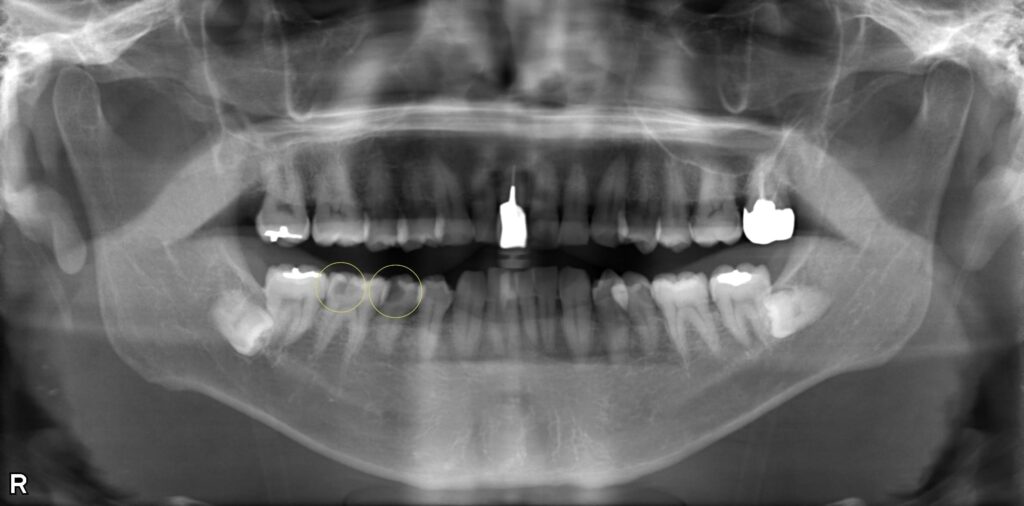

歯髄炎に対する抜髄・根管充填処置の症例

右下の痛みを訴えて来院されました。右下5番・6番に大きな虫歯ができており、歯の神経に炎症を引き起こしている「歯髄炎」という状態でした。 歯髄炎の場合は、炎症が根管内のどの部位まで進行しているかを診断します。 今回のケースでは、根の先まで炎症が進行しておらず、まだ感染を起こしていない状態でしたので、抜髄処置と同時に緊密な根管充填を行いました。 充填処置を即日に行うことで、感染にさらされる機会を最小限に抑えることができます。 術後の経過は良好で、根尖部に透過像もなく安定しています。

症例画像